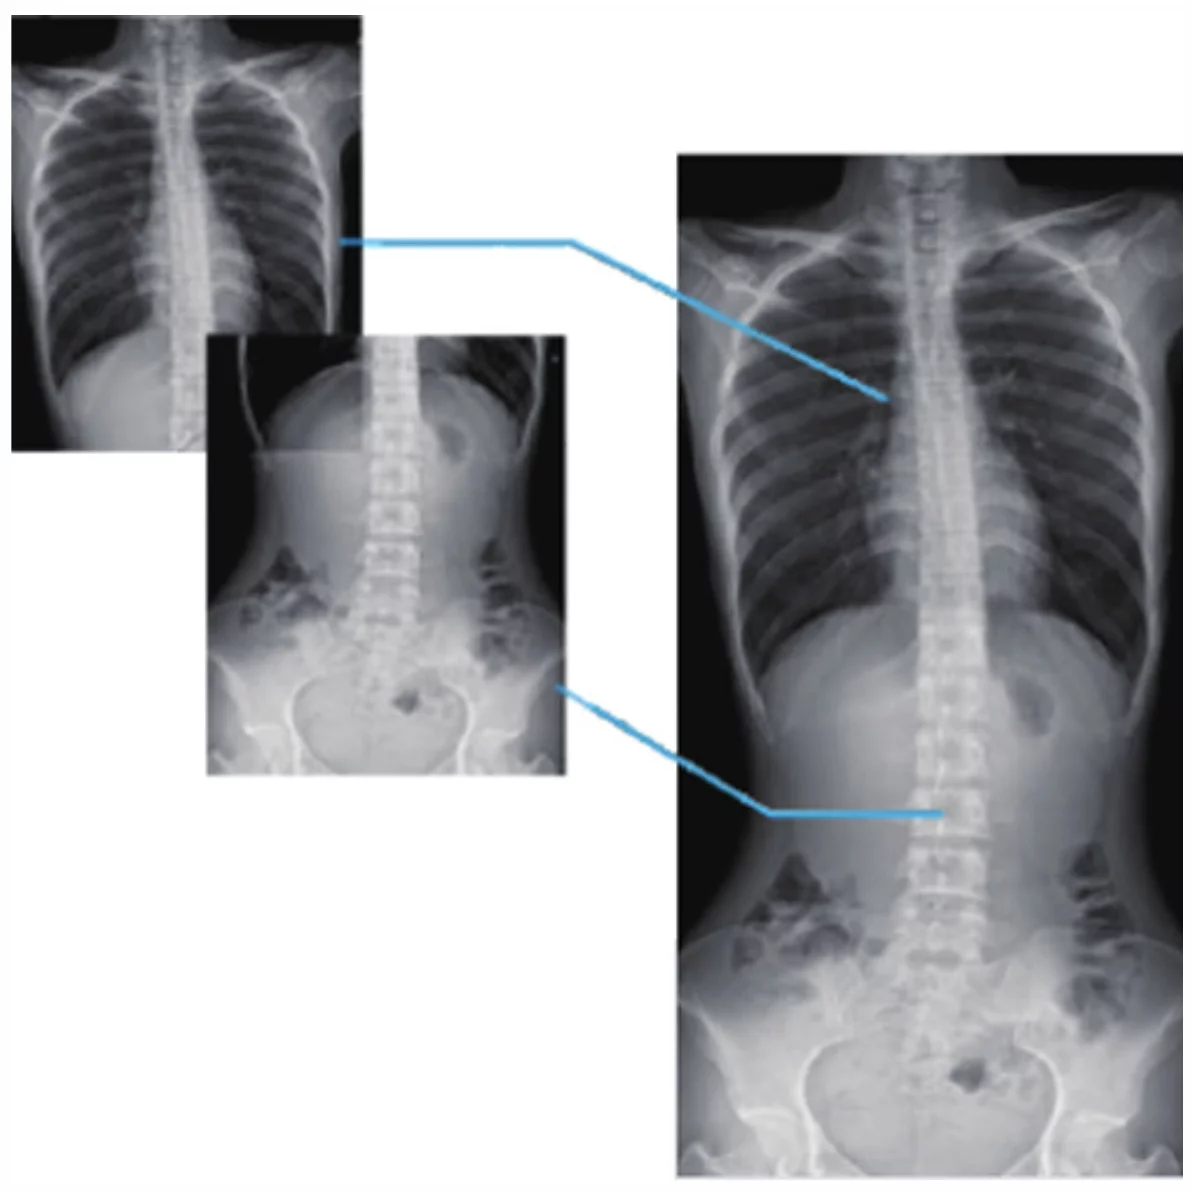

- Новая автоматическая система контроля дозы, получение более четкой информации об изображении при меньшей дозе облучения, снижение радиационного воздействия на врачей и пациентов. Интеллектуальное управление Ориентированность на людей и высокий уровень заботы Гибкое и эффективное многомерное перемещение Полное удовлетворение в различных положениях. Умные инновации Полнофункциональный динамический FPD Отличное изображение с широким охватом 17*17 большой размер динамического FPD, который обеспечивает большую площадь захвата, широкое поле изображения и полный охват изображения. Высокая частота кадров Высокая частота кадров позволяет получать изображения высокой четкости в динамическом режиме так же, как и в статическом. Самая высокая скорость съемки может достигать 30 кадров/секунду, четкие и гладкие динамические изображения. Функция автоматической сшивки Сколиоз и несущая деформация скелета нижних конечностей, предоперационная и послеоперационная панорамная съемка может непосредственно отражать степень и расположение поражения, обеспечивать надежную диагностическую основу для клинической практики. Полный позвоночник, полная панорамная съемка нижних конечностей, достижение одномоментной рентгенографии во время наблюдения сколиоза от шейного позвонка до хвостового позвонка или других повреждений.